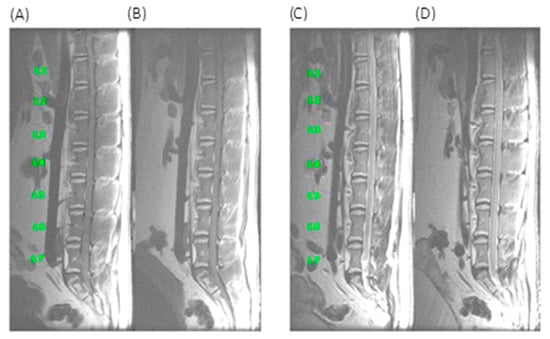

3.4. MRI